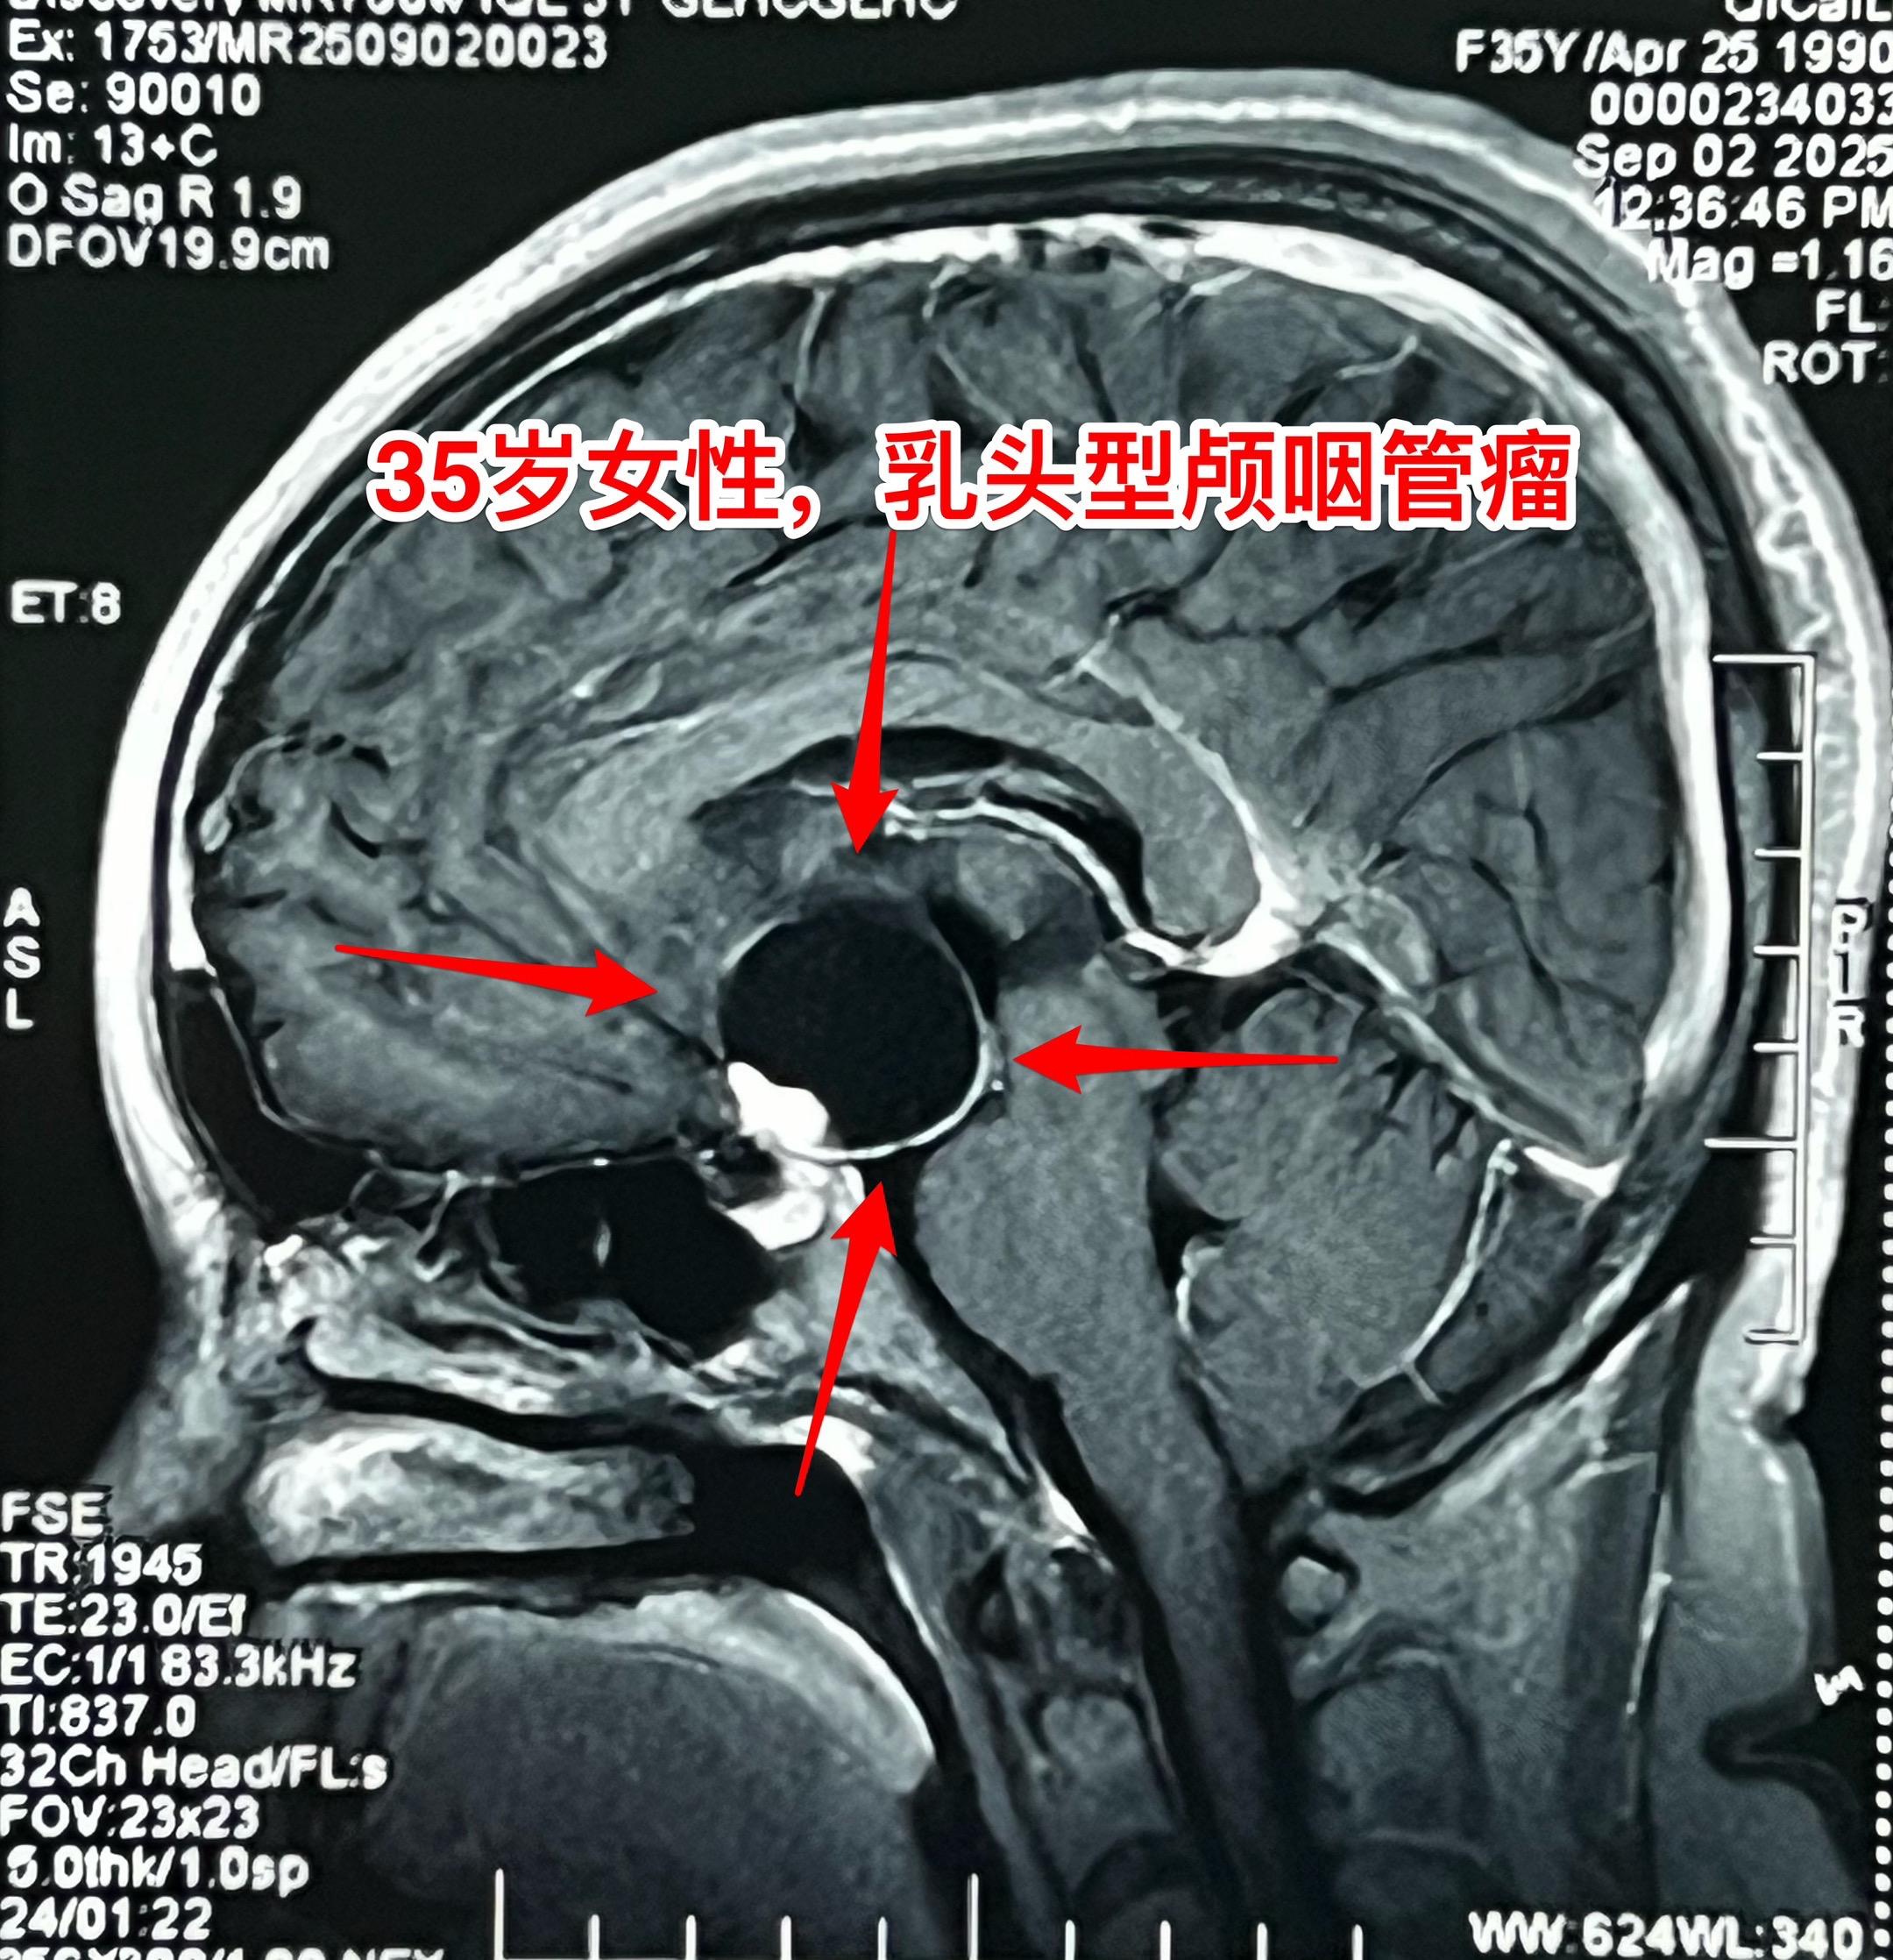

颅咽管瘤的症状科普。之前我多次讲过颅咽管瘤的症状,结合这个病人再说一次。 这个35岁女性在2025年8月发现了颅咽管瘤。 她两年前最开始出现生理周期紊乱、停经,这是下丘脑-垂体受损伤导致的内分泌系统功能障碍的表现。 一年前患者出现视力下降,越来越严重,一直到没有有效视力了才去就医,才发现这个颅咽管瘤。这是视神经-视交叉受到肿瘤压迫造成的。 在视力下降的同时病人出现长胖,体重显著增加。这也是下丘脑受损的表现。 病人在就诊